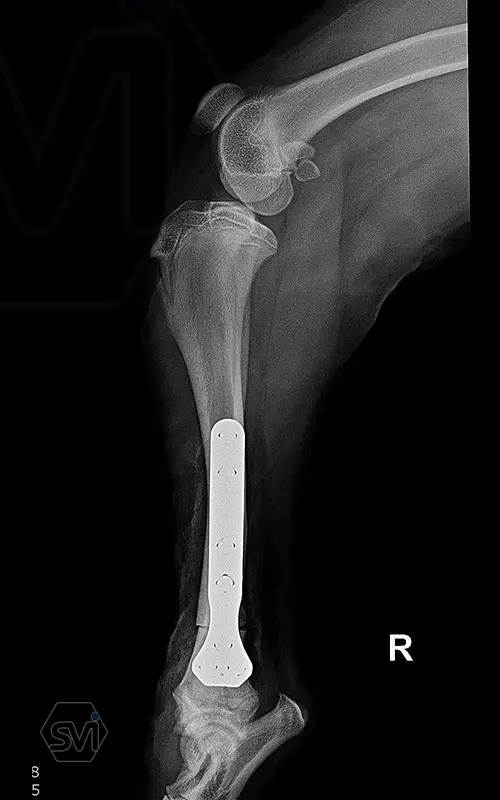

Multifunctional symmetrical long polyaxial locking plate - designed for the treatment of fractures close to joints

A special member of the polyaxial locking plate family is the multifunctional long plate, which is an extended version of the well-known symmetrical TPLO plate, with a 5-3 hole distribution. The plate also received a DCP hole to be able to create compression, and there is a mini-hole on the head end to facilitate the placement of the temporarily used K-nail. The burrs on the side facing the bone surface are intended to reduce the contact surface between the plate and the bone (limited contact).

The plate is a member of the large polyaxial locking family, suitable for 2.7-3.5-4.0 mm screws. We recommend it for fixaton of fractures close to joints, wedge osteotomies with axis correction (closing and opening), or for CWTO operations.